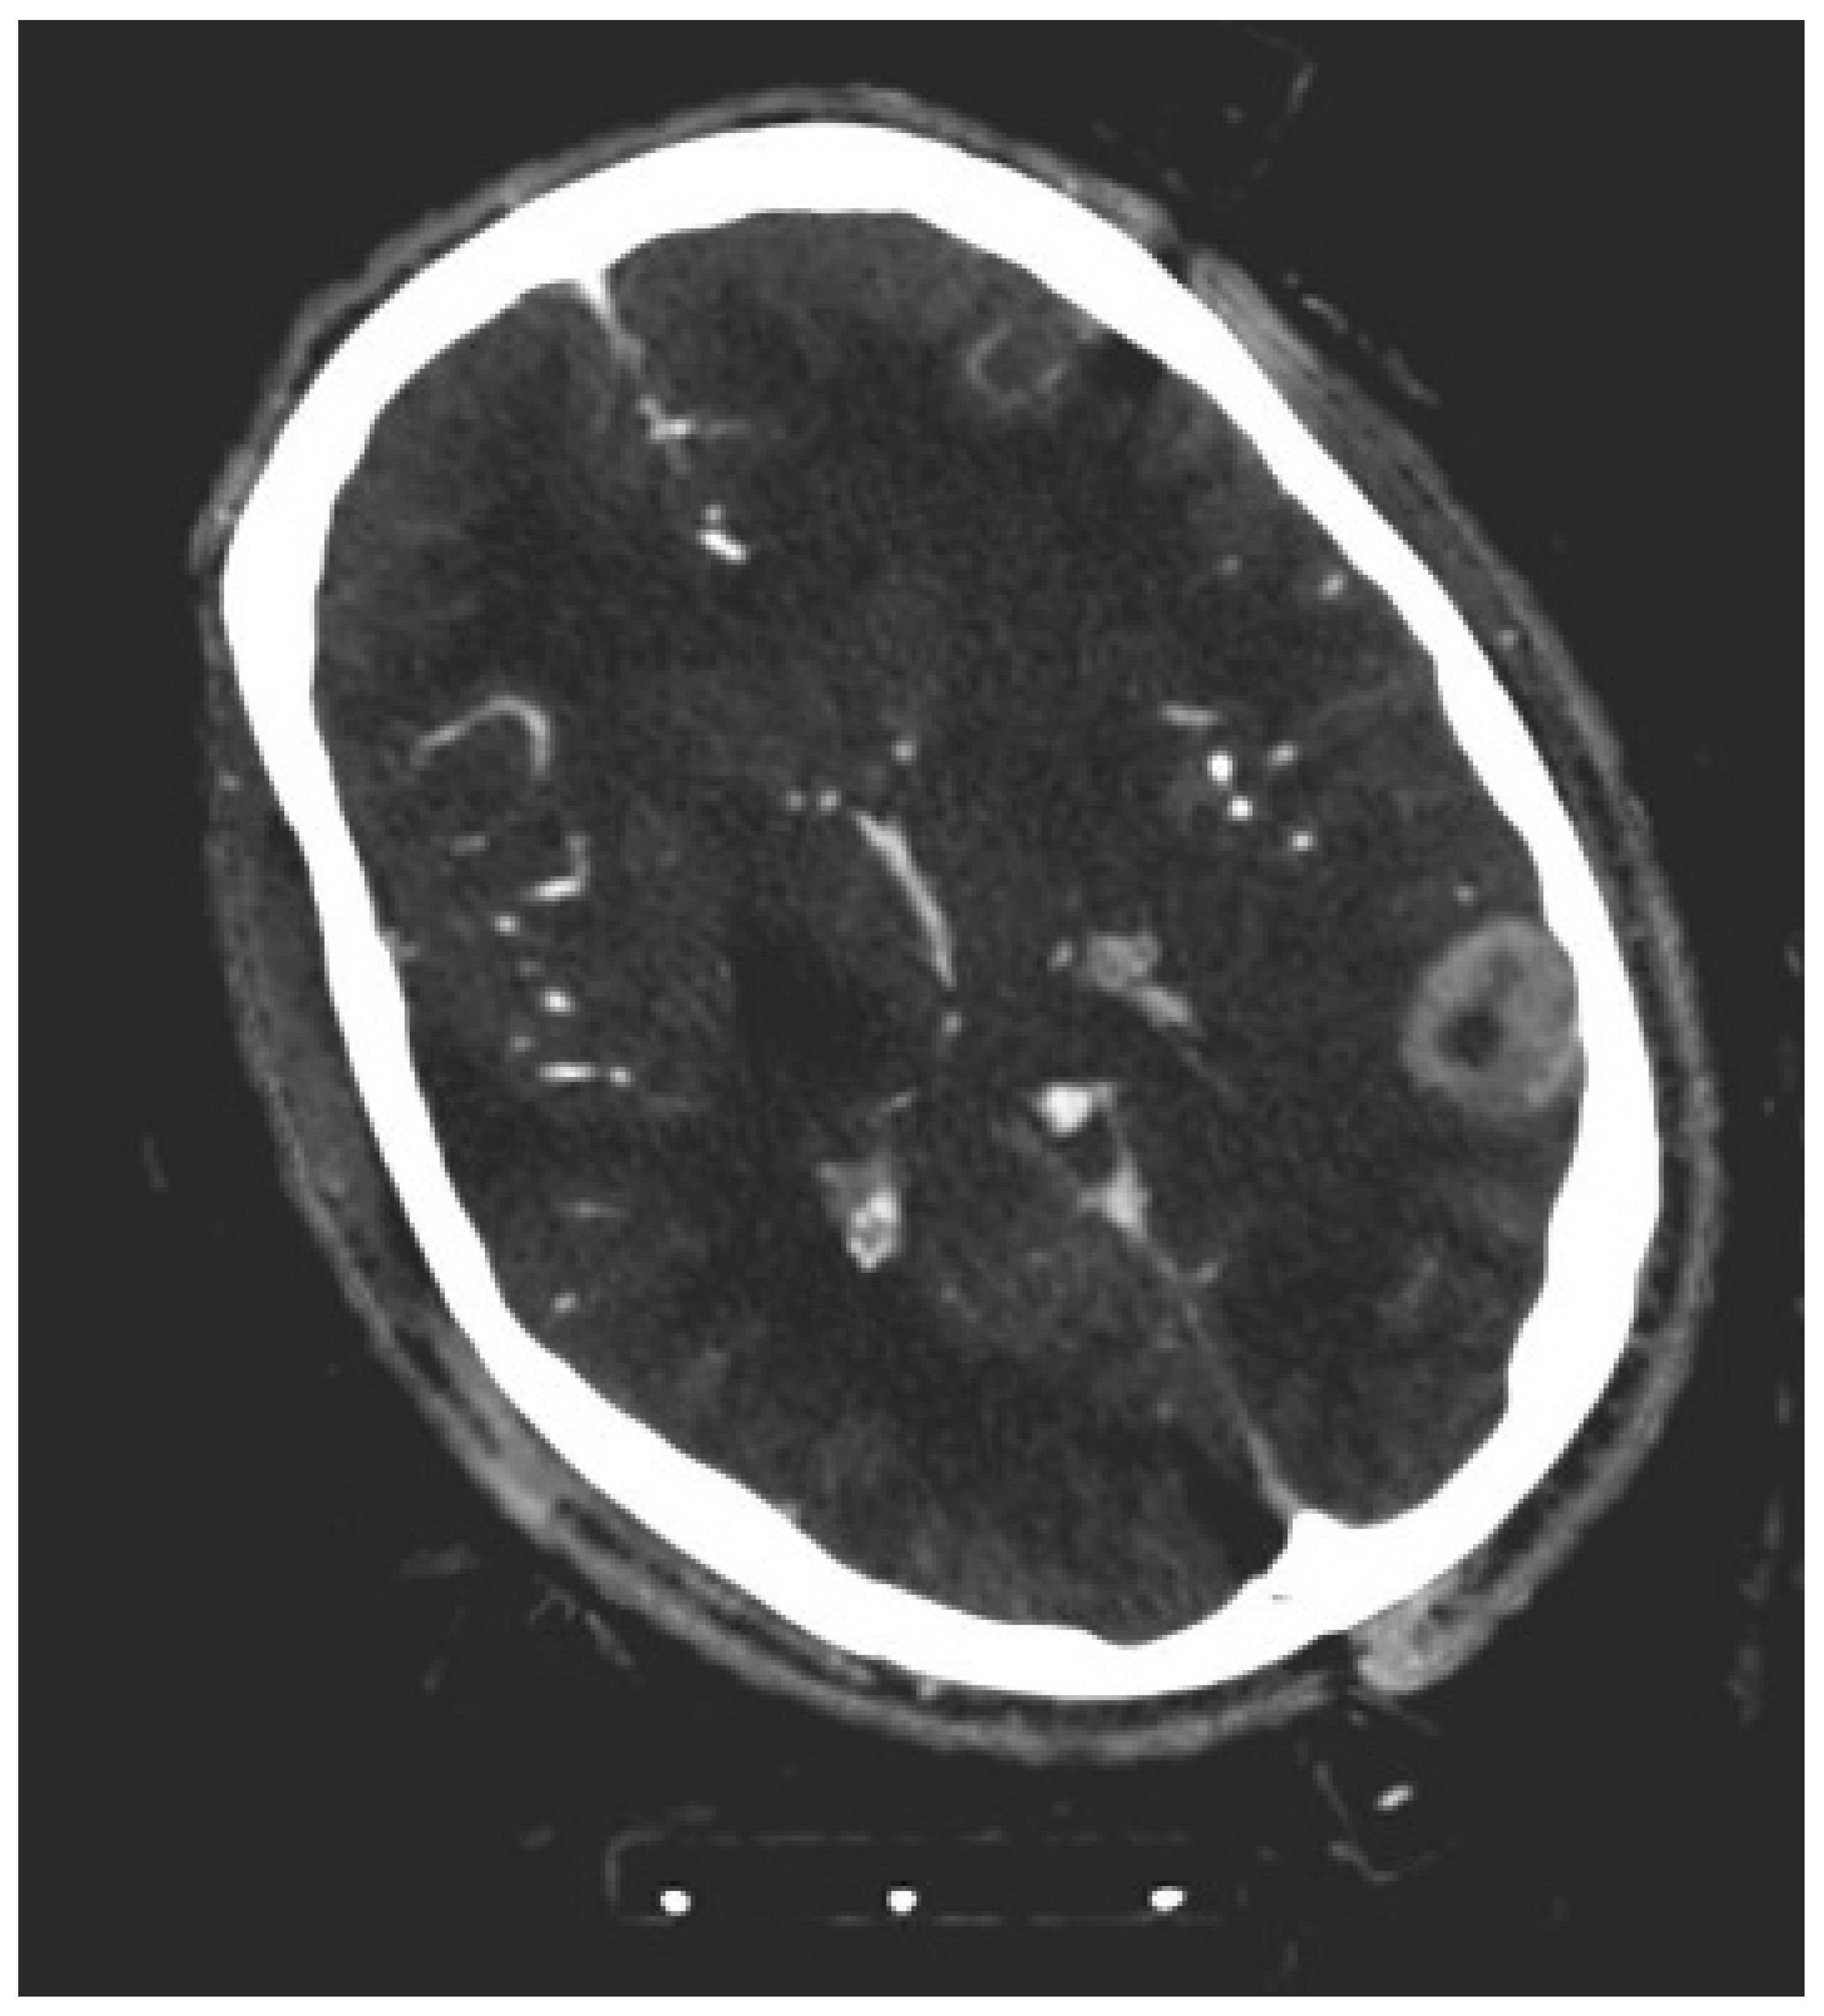

Differentiation of Intracerebral Tumor Entities with Quantitative Contrast Attenuation and Iodine Mapping in Dual-Layer Computed Tomography

2. Materials and Methods